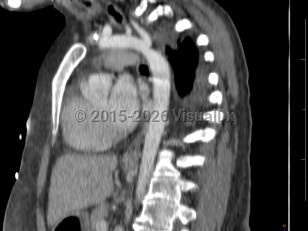

Coarctation of the aorta

Narrowing of the descending aorta distal to the take-off of the great vessels. Posterior costal arteries and internal mammary and scapular arteries provide collateral flow to the descending aorta. Usually congenital, although can be acquired as a consequence of inflammatory diseases affecting the aorta (eg, Takayasu arteritis). Clinical manifestations vary by age and associated cardiac defects, which may include bicuspid aortic valve, atrial septal defect (ASD), ventricular septal defect (VSD), patent ductus arteriosus, and D-transposition of the great vessels.